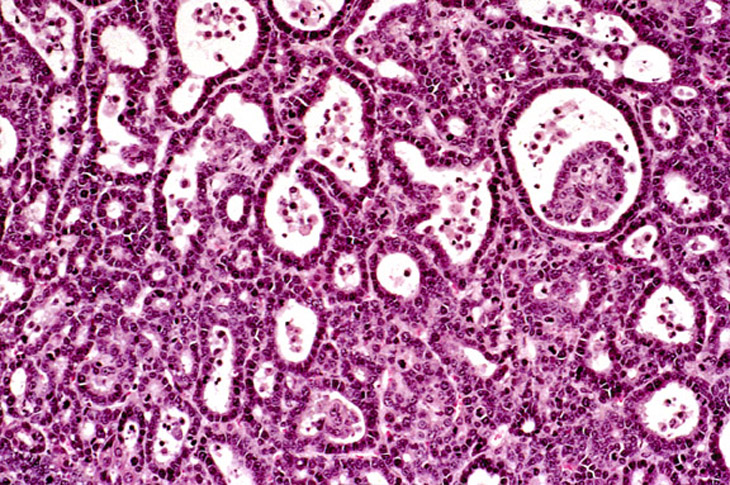

Ductular formation of hepatocytes in this 2-week old AL-TAg x AL-myc mouse has a predominantly centrilobular localization.

An altered hepatocyte focus is arising in an area of ductular formation in this 2-week old AL-TAg x AL-myc mouse.

Focal areas of bile duct proliferation also arise within areas of ductular formation in 2-week old AL-TAg x AL-myc mice.

Increased severity of focal bile duct proliferation associated with an area of ductular formation in a 3-week old AL-TAg x AL-myc mouse.

Areas of ductular formation and bile duct proliferation can be extensive in the livers of 3-week old AL-TAg x AL-myc mice.